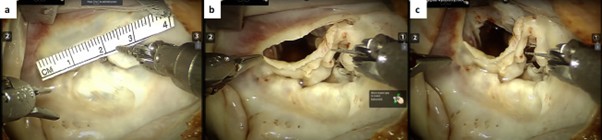

CO2 was used to flood the field at a flow rate of 2 L/min. A generous left atriotomy was made along Sondergaard’s groove, and the robotic dynamic atrial retractor was positioned to expose the mitral valve. With the aid of the robotic suction/irrigation system, the mitral valve was studied, and the leaflet coaptation was marked by measuring the long-axis length of the A2 and P2 segments. The mitral valve’s annulus was severely dilated with intrinsic posterior leaflet disease. The plan was to proceed with the myectomy portion and address the mitral valve pathology on the way out. A generous incision was made in the anterior leaflet from the medial trigone to the lateral trigone, leaving a 2 mm cuff of the anterior leaflet to the annulus to aid with the repair (Figure 3). The atrial retractor was then positioned to expose the interventricular septum through this incision.

Figure 3

Figure 3. (a) Measuring the distance from the medial to the lateral trigone to aid with closure planning. (b) A generous incision was made in the anterior leaflet from the medial trigone to the lateral trigone using Potts scissors, leaving a 2 mm cuff of the anterior leaflet adjacent to the annulus to aid with the repair. (c) Exposure of the interventricular septum and aortic valve through the mobilized mitral valve anterior leaflet.